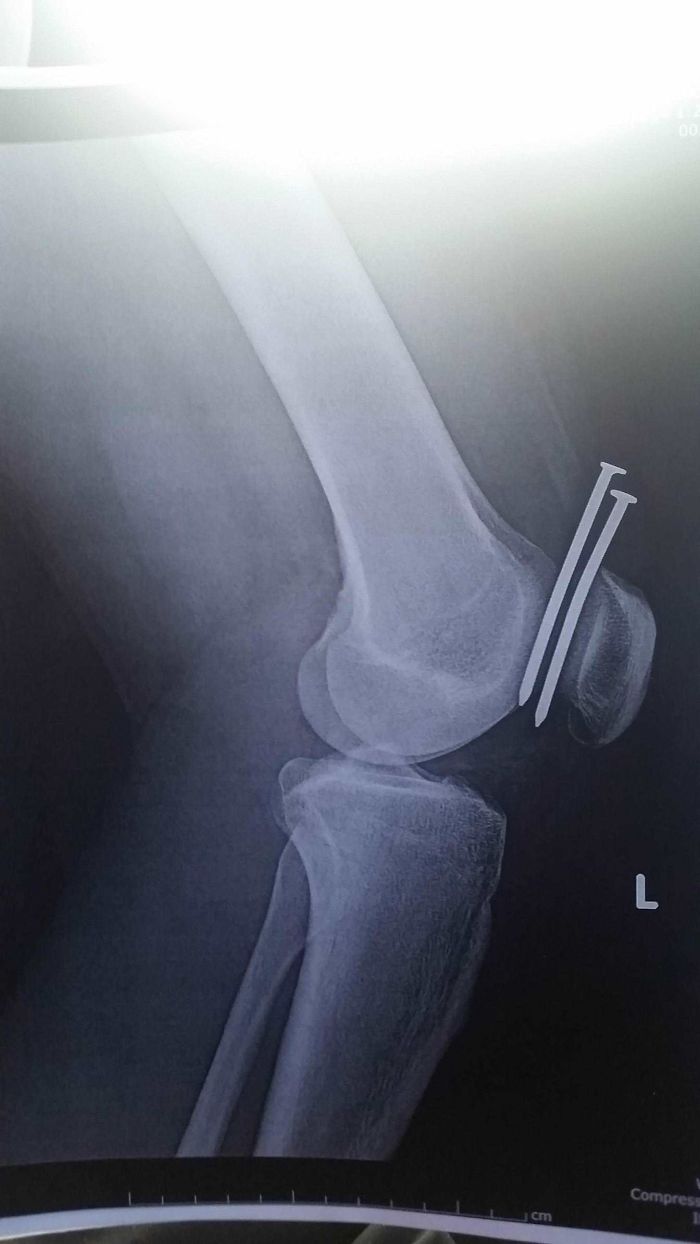

Este acróbata improvisado si me encantó como se salvó de la muerte. No se si se fracturó pero es una proeza.